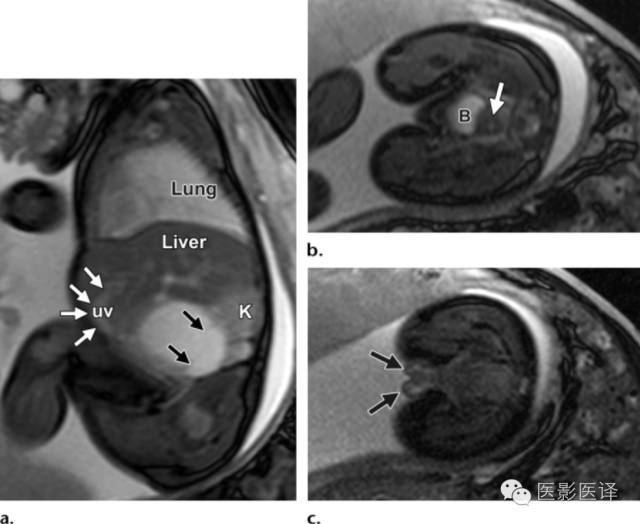

图8MR图像可清晰显示胎儿解剖。(a)稳态进动MR图像矢状位显示一囊肿内伴多发分隔(黑箭),该囊肿位于肝脏下缘、肾脏(K)前缘。可见脐静脉(uv;白箭)进入肝左叶。(b,c)稳态进动MR图像横断位显示胎儿子宫(图b中箭头所示)位于膀胱(B)后方,提示女性内生殖器,阴唇(图c中箭头所示),提示女性外生殖器。证实了女性生殖器存在也就可以支持卵巢囊肿的诊断;若显示为男性生殖器则可以将卵巢囊肿从鉴别诊断中排除。